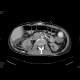

Kidney laceration

A hematoma in the posterior part of the right kidney, which is not enhancing. Ascites.

Radiology image - Kidney laceration: Abdomen, Kidney and adrenals: CT - Computed tomography